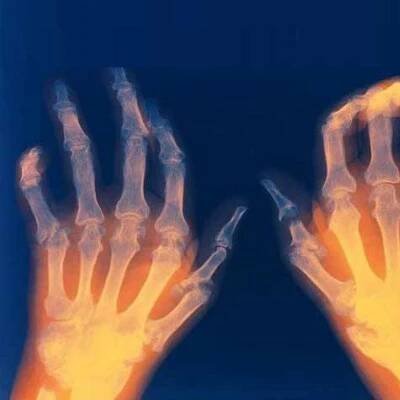

Ruce poškozené revmatoidní artritidou

Revmatická artritida

Artritida